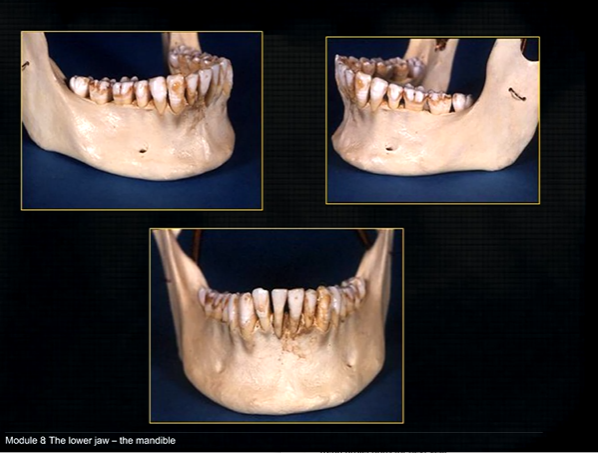

mandible - the lower jaw

mental prominence

body

mental foramina

dense bony prominence of the external oblique ridge

angle

coronoid process - and ascending rami on both sides????

anterior lingual/inner aspect of the mandible

bony spurs

genial tubercules - muscles of the tongue and neck attach here

lingual pit

mylohyoid ridge - mylohyoid attaches to form the floor of mouth

mandible varies in cross sectional thickness

left hand side of the mandible buccal surface has been removed

roots of the teeth protrude in the underlying trabecular bone

inferior dental nerve

mental nerve - coming out of the mental foramen

reveals honeycombed pattern of trabecular bone

dense outline of the individual sockets of the teeth

cortical bone which forms the lower border